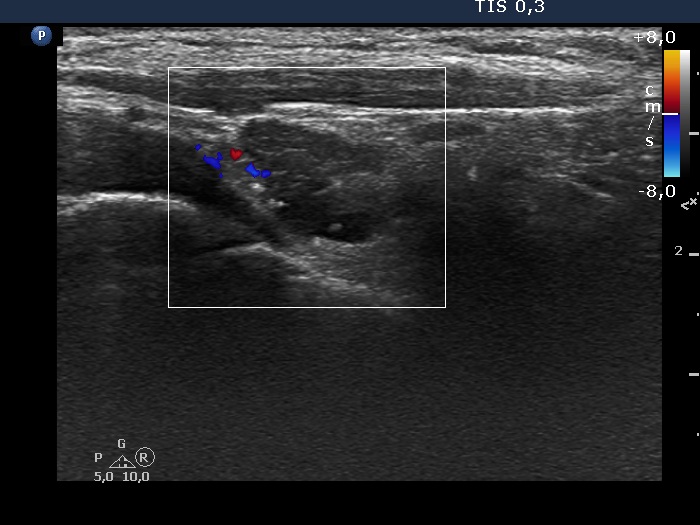

Right lobe, longitudinal scan

Right lobe, longitudinal scan, color Doppler mode.